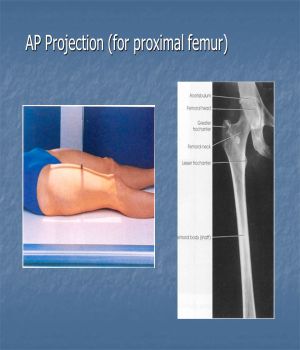

X-ray Both Thigh/Femur AP & LAT | Pricing in Delhi at Ganesh Diagnostic

.jpg)

.jpg)